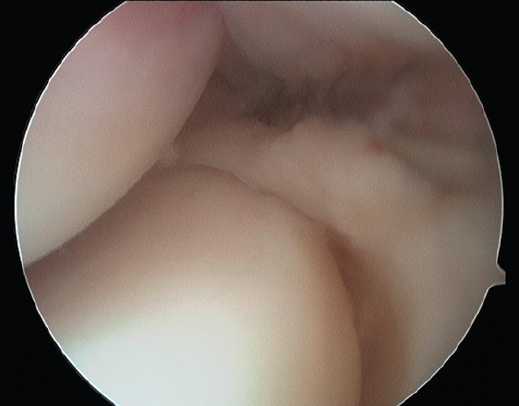

Plica sinovial

La presencia de una plica sinovial radiocapitelar patológica es una fuente potencial de dolor en la cara lateral del codo(31,32). Normalmente pueden existir plicas o pliegues de sinovial como remanente del desarrollo embrionario normal de la membrana sinovial(33). Estas plicas no tienen una función conocida y normalmente no causan ningún síntoma(34), excepto cuando el tejido se hipertrofia tras un traumatismo o por actividades repetitivas, produciendo roce en la articulación radiocapitelar durante el movimiento (Figura 11).

Figura 11. Imagen artroscópica de un codo derecho desde el portal anteromedial. Se aprecia una plica posterolateral.

Para el diagnóstico diferencial con la tendinopatía lateral de codo, la exploración física típica será la que nos haga sospechar esta entidad, acompañada de algunos hallazgos en las pruebas de imagen.

Los principales síntomas diferenciales son dolor selectivo a la palpación en el soft point (el centro del triángulo formado por la cabeza del radio, el epicóndilo y la punta del olécranon) y en la parte posterior de la articulación radiocapitelar; además, puede asociar déficit de extensión, dolor posterolateral durante el final de la extensión y con la pronación-flexión. Los pacientes también pueden describir sensación de tirantez o resalte con la movilidad. Realizar un test de flexión-pronación (donde el examinador realiza flexión pasiva del codo pronado) puede reproducir un chasquido(32).

Figura 12. Imágenes de resonancia magnética de un codo izquierdo. Se aprecia una plica posterolateral de codo en el plano coronal (A) y en el plano sagital (B y C).

La RM permite visualizar un tejido similar a un menisco en la cara lateral de la articulación radiocapitelar que se interpone entre la cabeza radial y el capitellum (Figura 12). Las plicas pueden localizarse en el lado anterolateral, en el posterolateral o en ambos, siendo más frecuente la localización posterolateral. La RM nos permite medir su grosor, así como su longitud. El grosor medio de las plicas patológicas suele estar en torno a 3,7 ± 1,0 mm, que es significativamente más grueso que el valor de una plica normal (1,8 ± 1,4 mm)(6). La longitud del pliegue medida en coronal y sagital (9,4 ± 1,6 y 8,2 ± 1,7 mm, respectivamente) también es mayor que los valores normales (3,9 ± 1,5 y 4,3 ± 1,5 mm)(35). Se debe tener en cuenta que no todas las plicas son patológicas ni sintomáticas, independientemente de su tamaño. Es necesario apreciar edema en el tejido que conforma la plica o a su alrededor y tener una clínica compatible. La artrorresonancia puede ser de utilidad en caso de dudas.